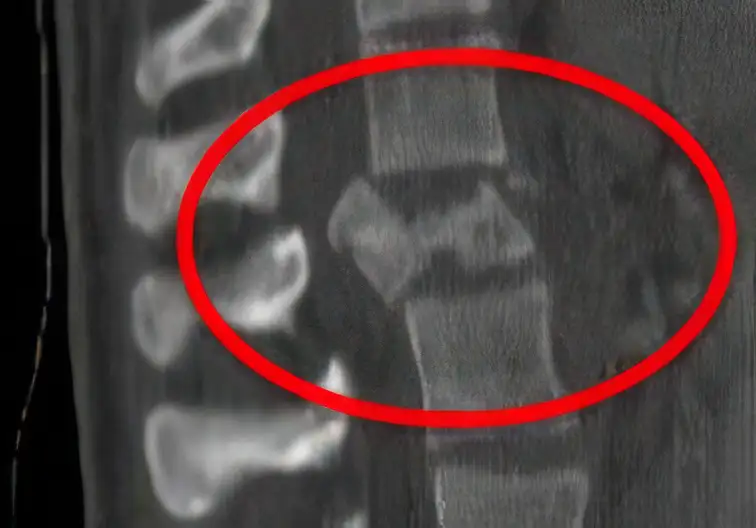

Bei einer Berstungsfraktur brechen sowohl die Vorder- als auch die Hinterkante des Wirbelkörpers. Durch Knochenfragmente der Hinterkante kann es zu einer Einengung des Spinalkanals kommen. Befindet sich die Fraktur auf Höhe des Rückenmarks, droht eine Querschnittlähmung (Paraplegie); liegt sie auf Höhe der Cauda equina, können partielle Lähmungen auftreten.

Da Berstungsfrakturen als potenziell instabil gelten, müssen sie in der Regel operativ stabilisiert und bei ausgeprägter Deformität zuvor aufgerichtet werden. Dies erfolgt mit einem internen Fixationssystem aus Schrauben und Längsstangen.